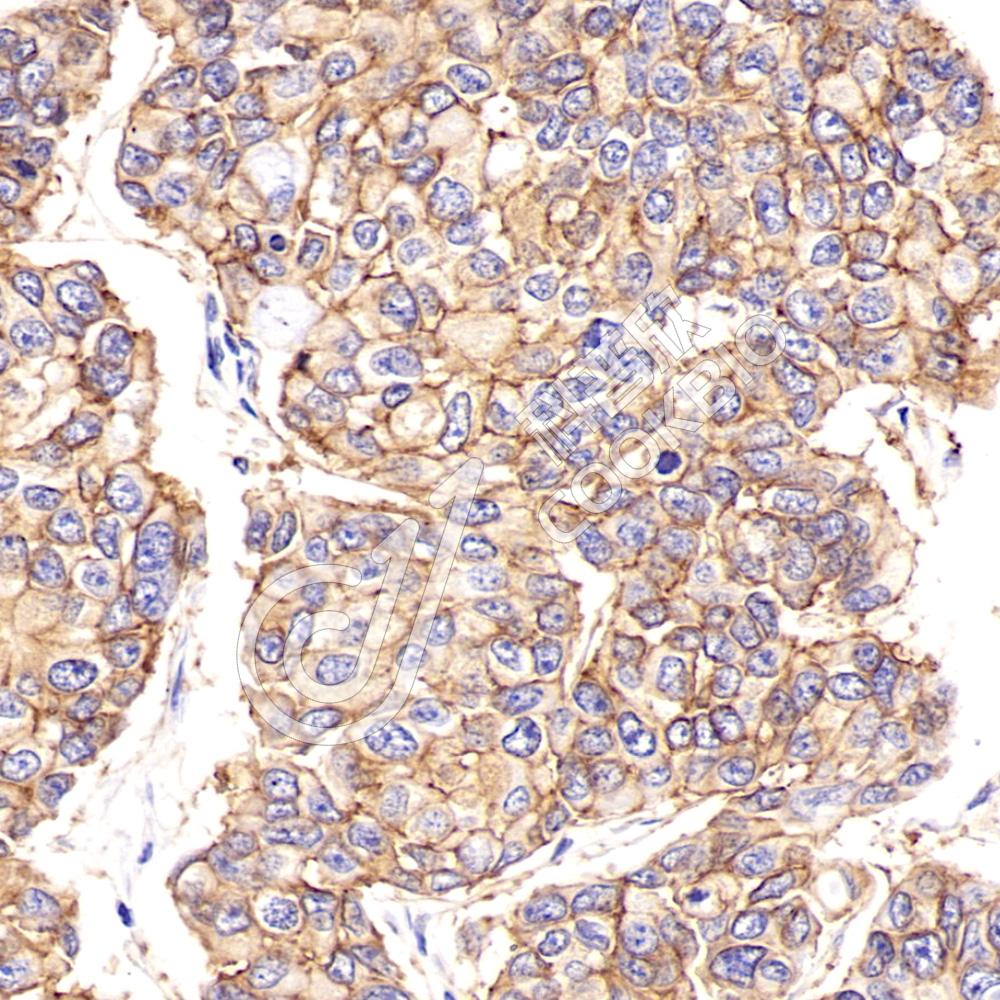

IHC检测ErbB2/HER2蛋白(货号 K1341913).

样品: 人乳腺癌, 4%多聚甲醛 (货号KSG1101) 固定12-24小时.

抗原修复: 柠檬酸抗原修复液(干粉, pH 6.0) (KSG1201), 98℃, 20分钟.

—抗: 1: 800稀释, 4℃ 孵育过夜.

二抗: S-vision免疫组化多聚二抗(山羊抗兔),即用型 (货号KB3906), 室温孵育20分钟.